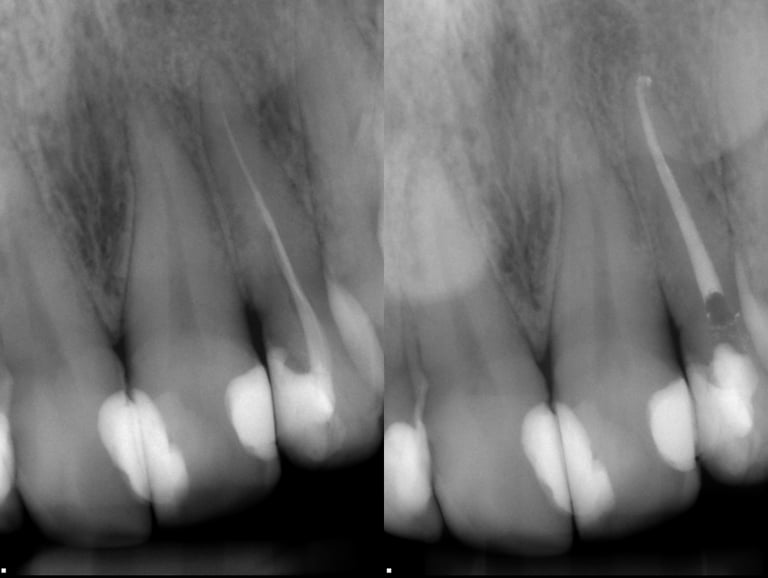

Gallery 1: Initial Cases

Initial Root Canal Cases with preoperative and postoperative radiographs.

#2 RCT with 4 canals

#19 RCT with 4 canals

#3 RCT with 4 canals

#14 RCT with extreme calcification & 4 canals